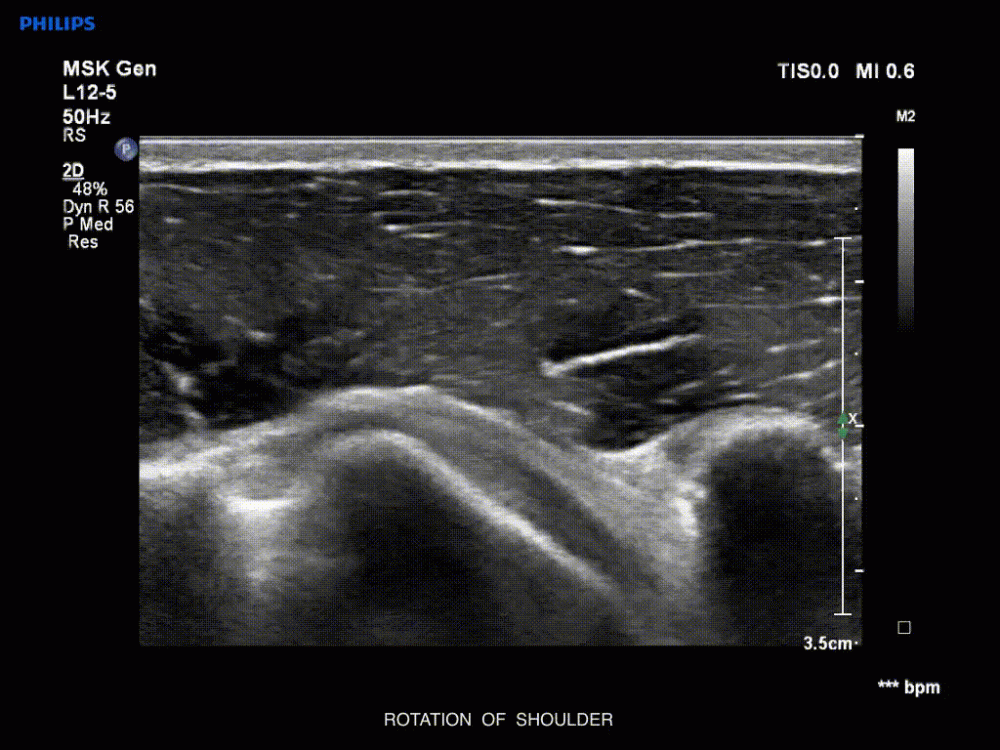

- Épaule : patient assis, main sur la cuisse ou derrière le dos.

- Douleur d’épaule : recherche d’un épanchement, d’une rupture de la coiffe des rotateurs ou d’une luxation.

- Épaule : approche antérieure (gouttière bicipitale), latérale (sus-épineux), postérieure (capsule). Rechercher : épanchement, luxation, rupture de la coiffe.